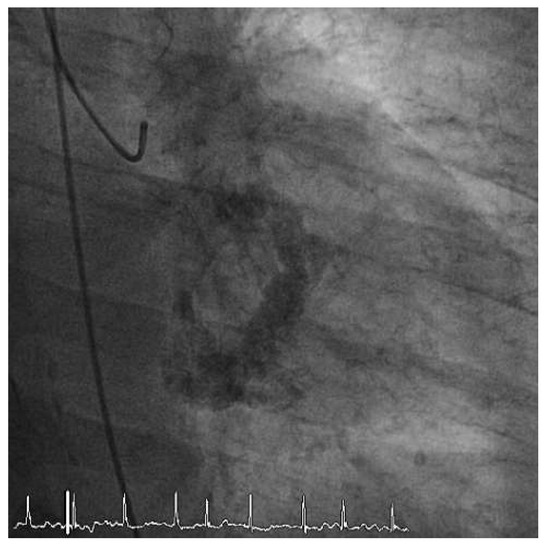

Worldwide First Surgical Implantation of a Transcatheter Valved Stent in Mitral Position

Case report